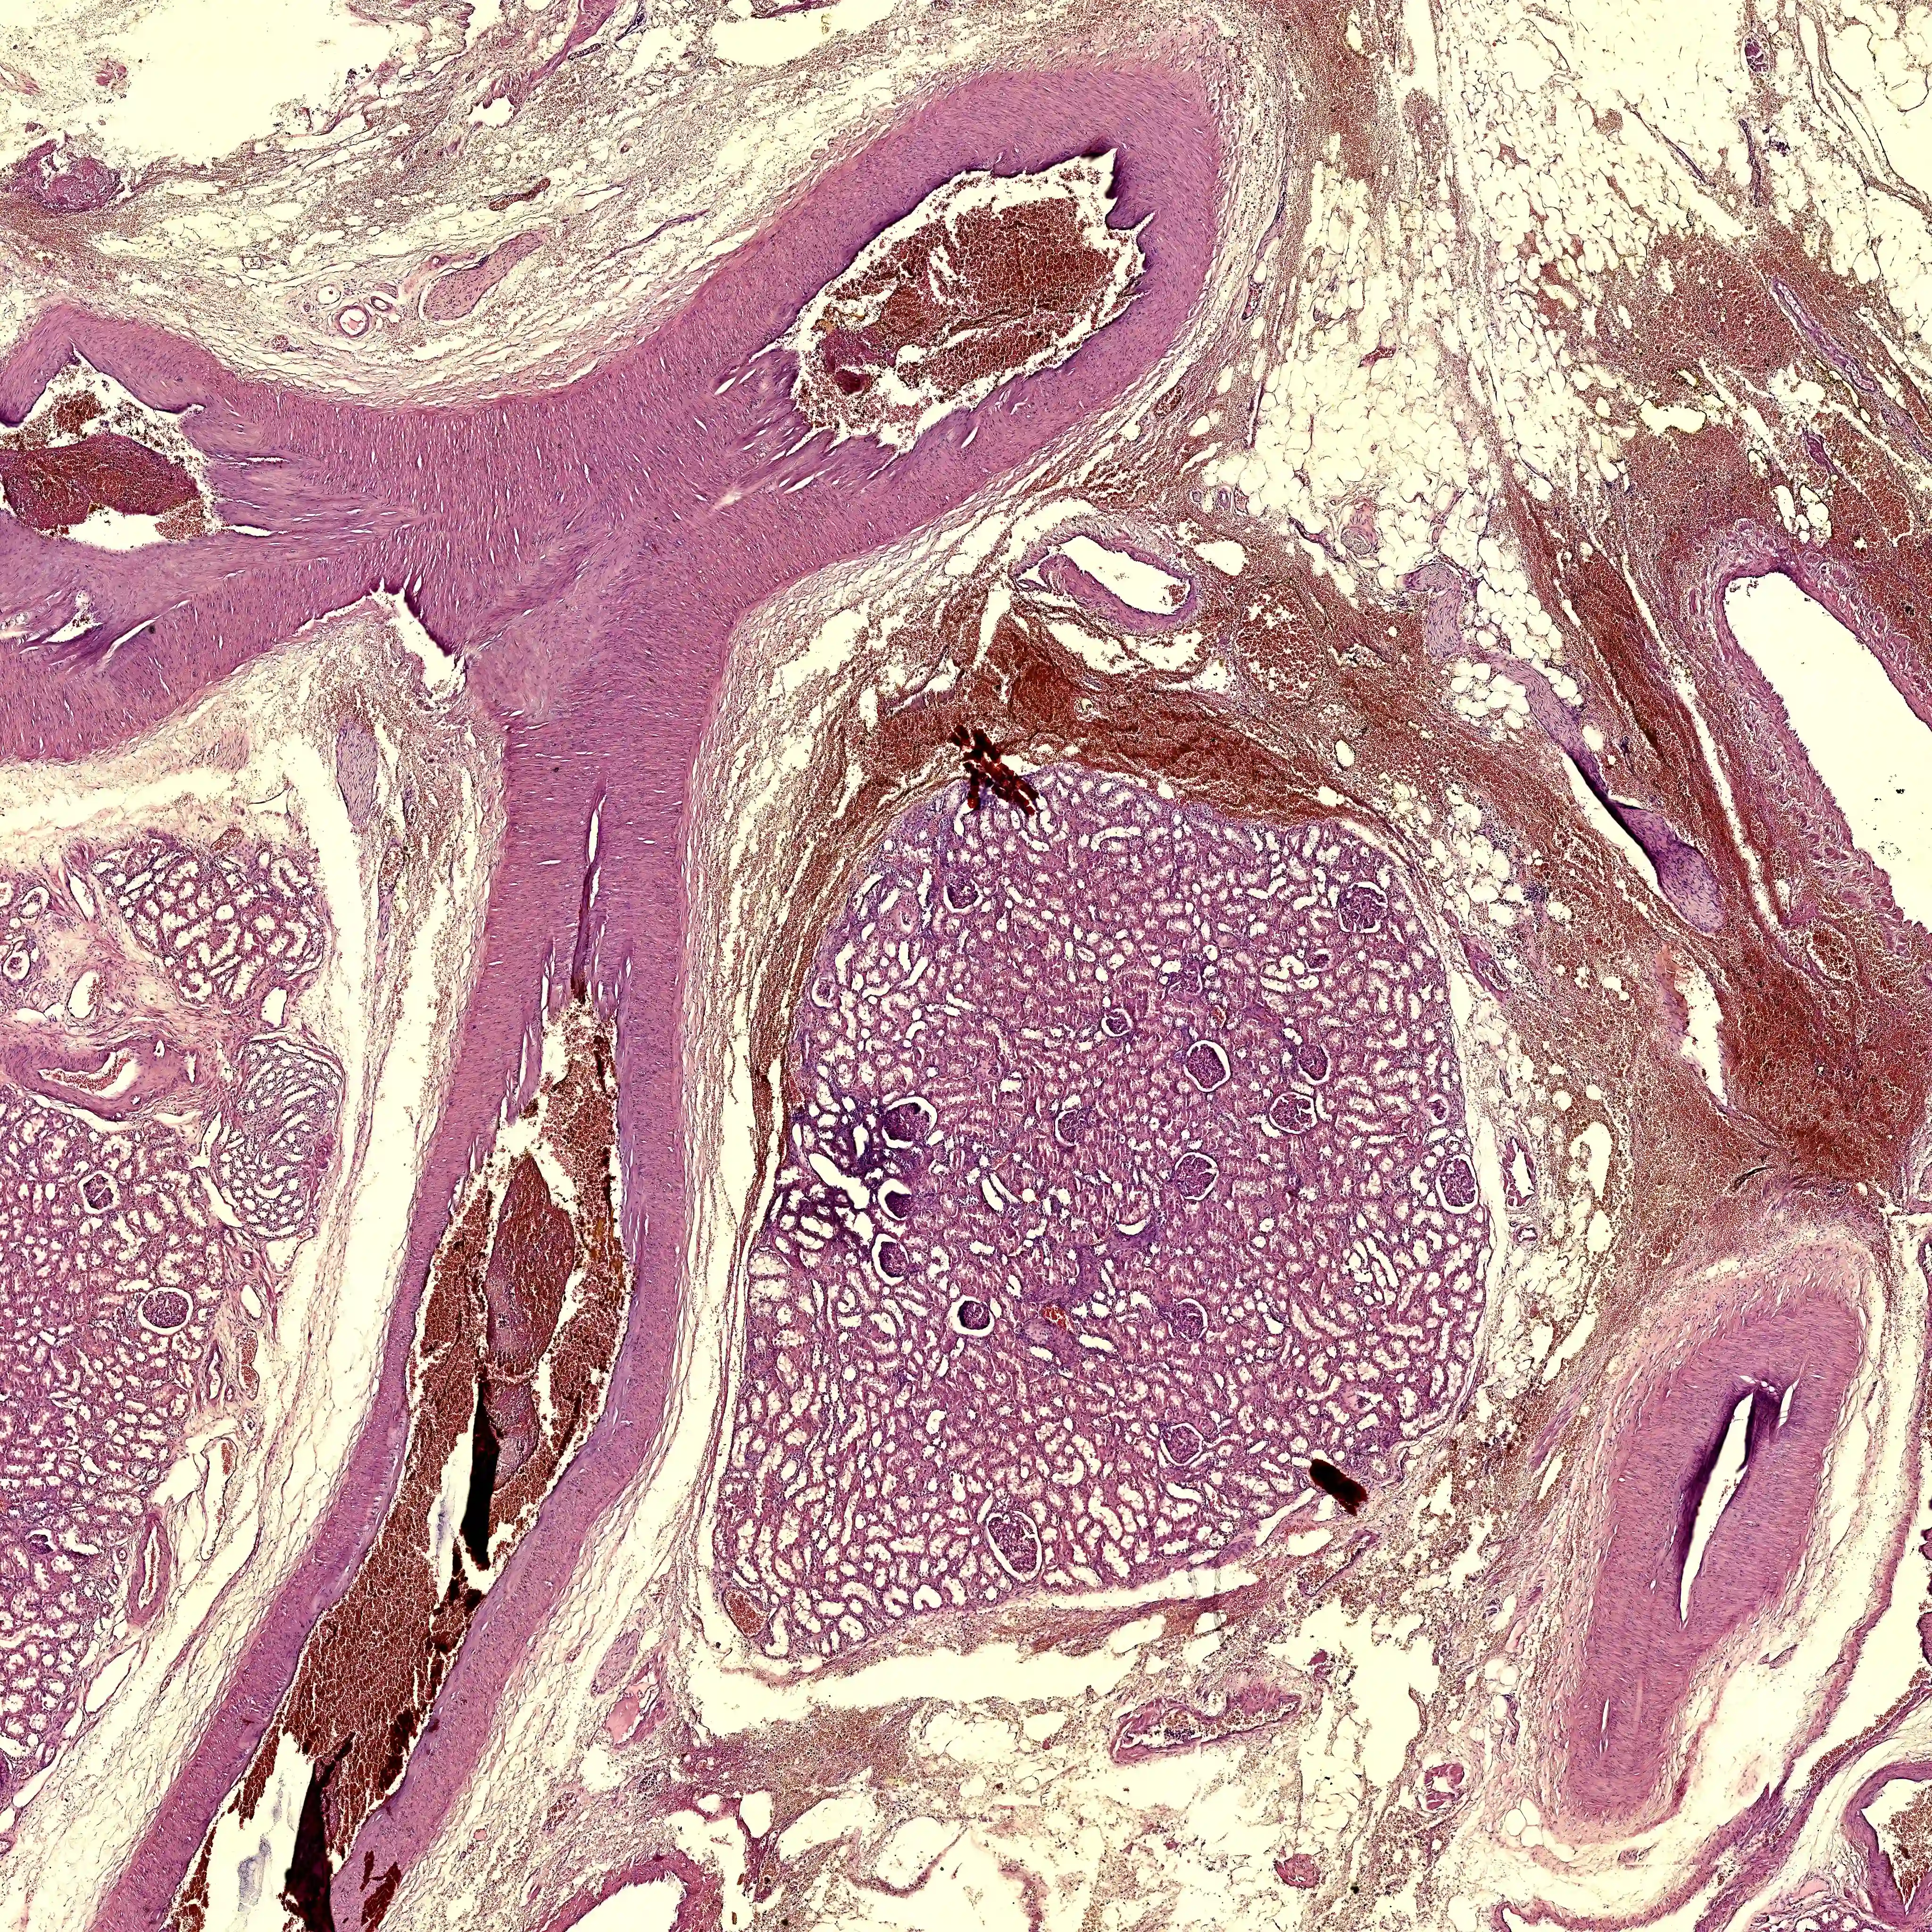

Over 120 scanned histology slides